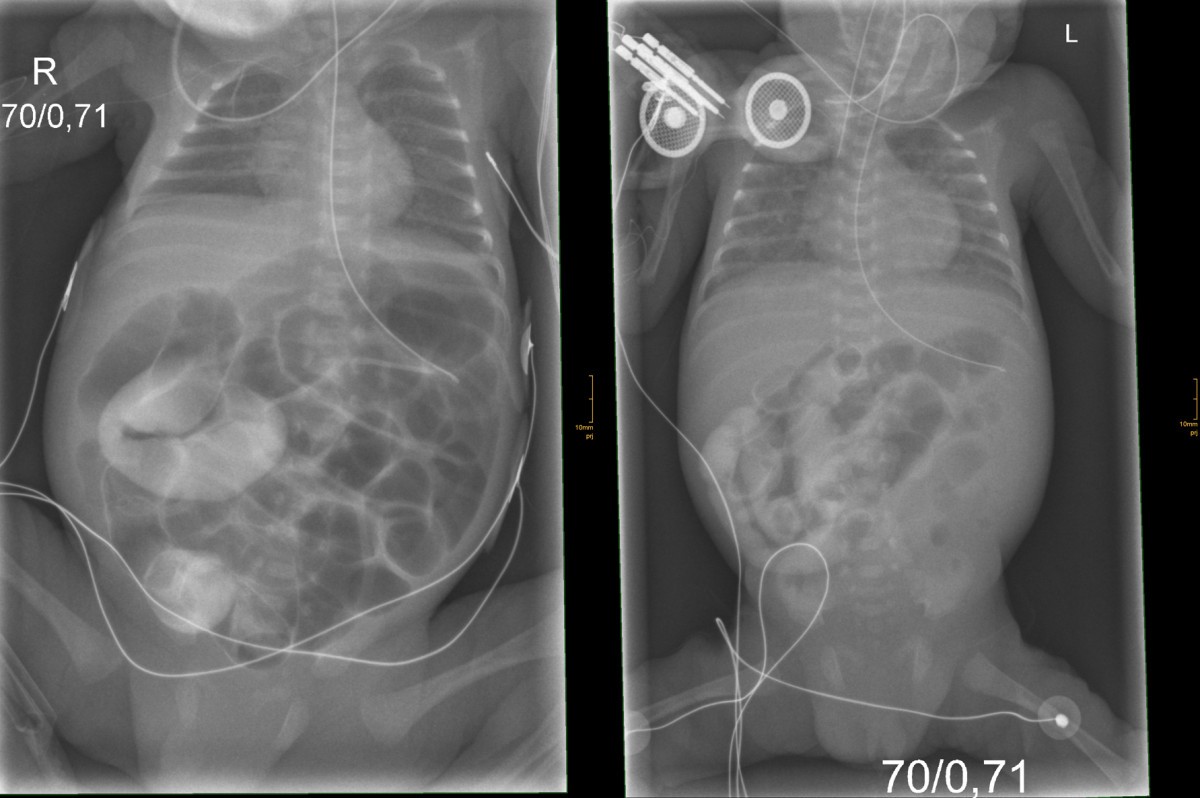

Meconium Ileus filling defect in the distal small bowel with small Meconium Ileus Differential Diagnosis Learn about the differential diagnosis, clinical presentation, radiologic studies. Antenatal diagnosis of meconium ileus is possible based on sonographic features suggesting hyperechoic masses (inspissated meconium in the terminal ileum), dilated bowel,. Can be used in cases of simple meconium ileus that does not. Meconium ileus is a small bowel obstruction caused by thick and sticky meconium, often seen in infants. Meconium Ileus Differential Diagnosis.